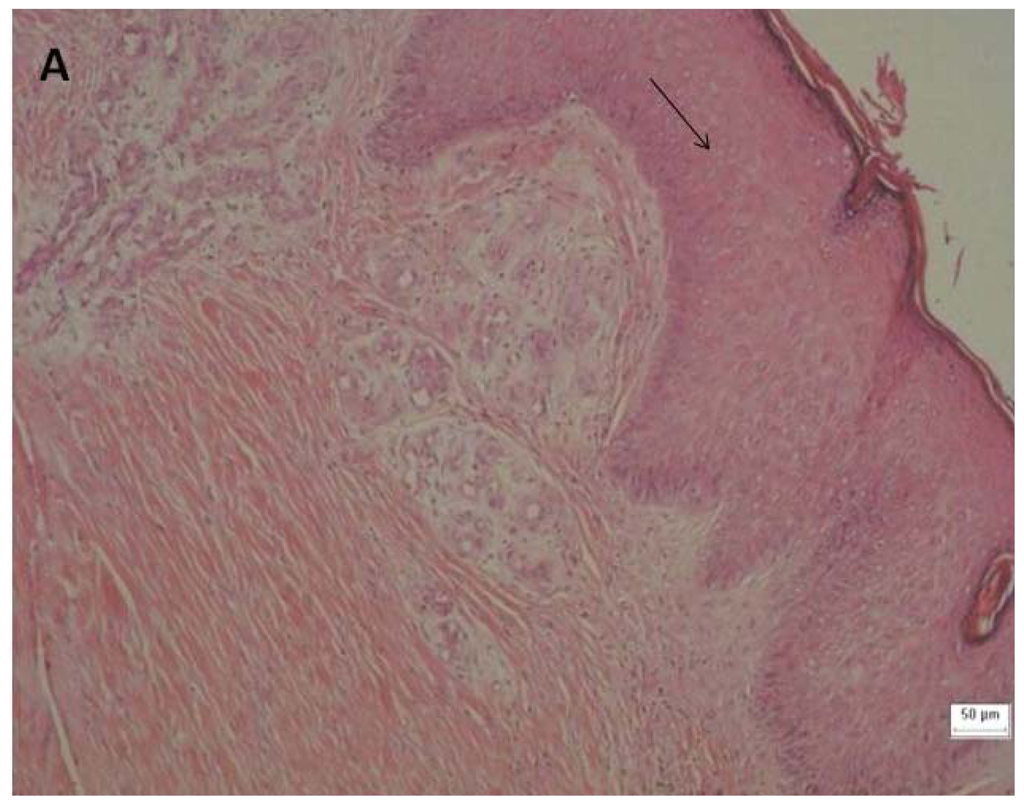

Figure 3.

Histology of the venous ulcers. The tissue was stained with hematoxylin and eosin (H & E) to visualize the cellular morphology. Samples A, B and C were collected prior to (1→3)-β-glucan treatment. The following magnifications are shown: 100 × H & E stain for A; 400 × H & E stain for B and C. (A) The arrow indicates epithelial hyperplasia at the edge of the ulcer. (B) Arrow No. 1 shows reactive and reparative epithelial changes in the stratified squamous epithelium and the other arrows show inflammatory cell infiltration, including neutrophil (arrow No. 2), plasmocyte (arrow No. 3) and lymphocyte (arrow No. 4). (C) Arrow No. 1 indicates angiogenesis associated with edema and arrow No. 2 indicates fibroblast.